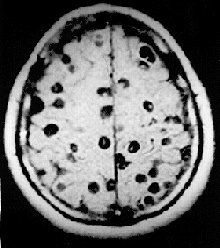

| Magnetic resonance image of neurocysticercosis demonstrating multiple cysticerci within the brain. | |